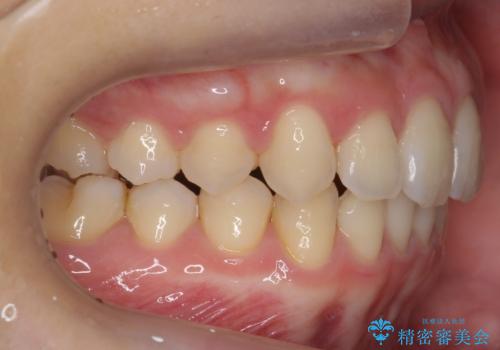

深いかみ合わせ 出っ歯の治療 インビザラインで

- 前歯の前突を主訴に来院。

かみ合わせが深く、また奥歯のかみ合わせも全体的に上が前にずれていました。

抜歯矯正も難しく、非抜歯矯正も歯の移動量が多くいずれにしても難易度が高い状態でした。

時間はかかりますが非抜歯で治療することにして、インビザライン矯正とワイヤー矯正を交互に行い仕上げました。

インビザライン矯正だけでなく、途中ワイヤー矯正もはさみました。前歯のかみ合わせが深く、本当に大変な治療でしたが協力度も高く非抜歯で上の奥歯を後ろに動かすことができました。